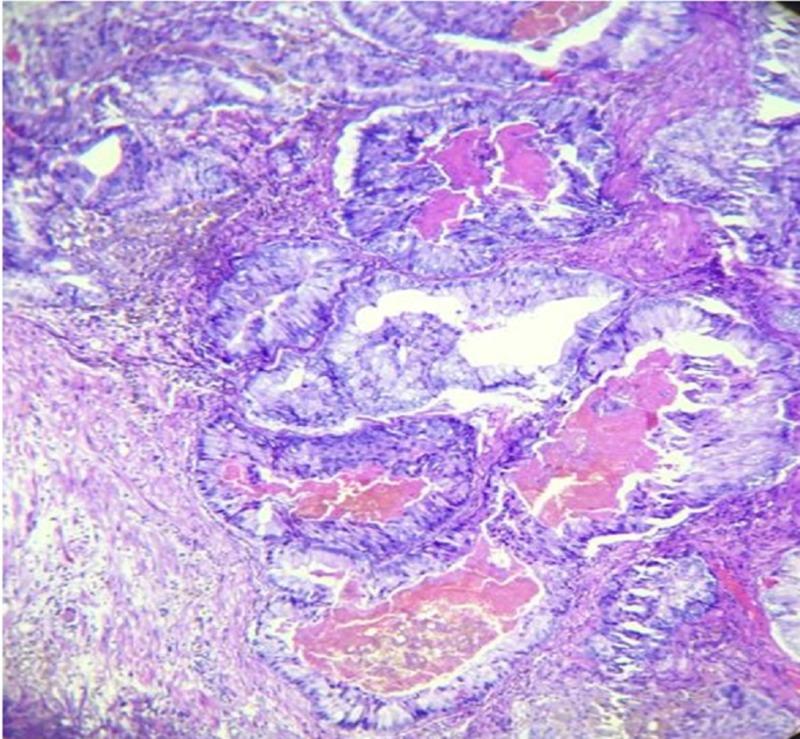

Prostatic ductal adenocarcinoma, is an uncommon entity in the spectrum of prostatic carcinoma. Clinically it is different from common prostatic acinar adenocarcinoma. It is usually more aggressive than prostatic acinar adenocarcinoma. We are presenting a case report on prostatic ductal adenocarcinoma, a cystic variant of prostatic carcinoma in a 55-year-old man who complained of obstructive urinary symptoms with mildly raised prostate-specific antigen (PSA). On further evaluation in our radiology department a cystic lesion with enhancing polypoidal soft tissue component was noted in prostatic parenchyma. Histopathology confirmed the diagnosis of ductal adenocarcinoma.

前列腺导管腺癌是前列腺癌谱系中一种不常见的类型。在临床上,它与常见的前列腺腺泡腺癌不同。它通常比前列腺腺泡腺癌更具侵袭性。我们报告一例前列腺导管腺癌病例,这是一名55岁男性的前列腺癌囊性变异型,他主诉有梗阻性排尿症状,前列腺特异性抗原(PSA)轻度升高。在我们放射科进一步评估时,发现前列腺实质内有一个伴有强化息肉样软组织成分的囊性病变。组织病理学确诊为导管腺癌。